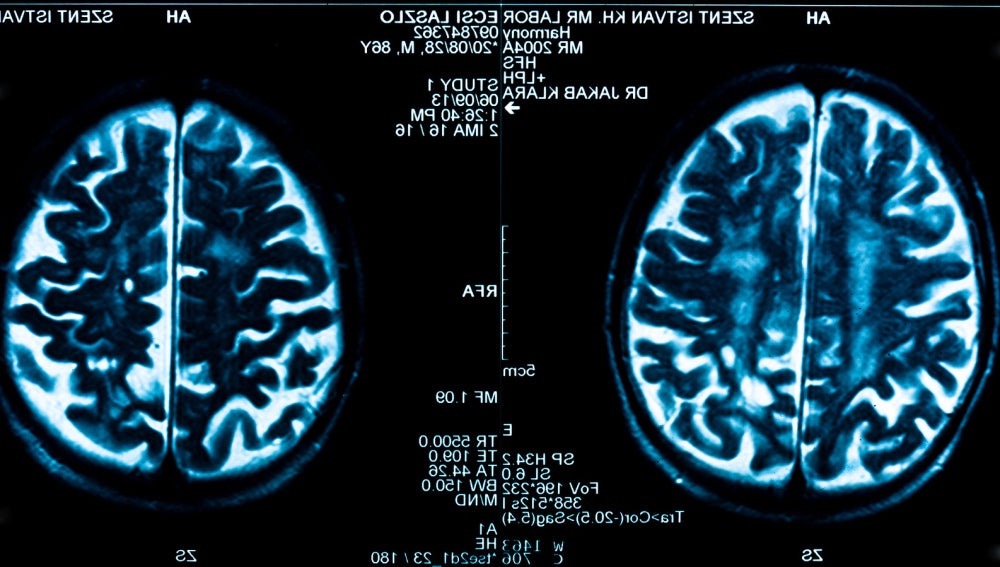

Contenidos virtuales para la rehabilitacion de pacientes con dano cerebral | Sinc